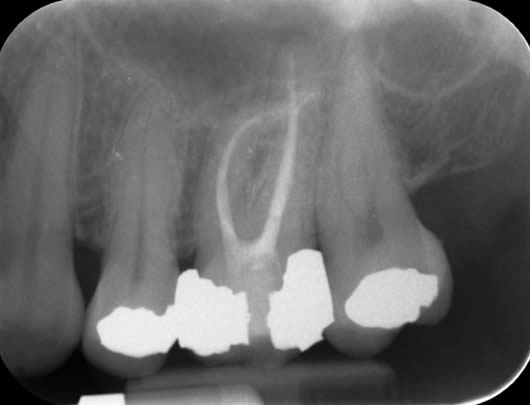

This patient presented with a history of a dull pain and swelling from his upper left second molar (UL7). The tooth had a crown and was tender when tapped. A radiograph (X-ray photograph) showed that there was a large shadow around the roots. This shadow indicates bone loss caused by infection within the root canals. The diagnosis for this tooth was ‘Chronic apical periodontitis’; and the treatment options were either extraction or root canal treatment. After discussion with the patient, we decided to proceed with root canal treatment. As the crown was in good condition, we decided to keep it in place and access through the top of it. This way, a new crown would not be needed after our treatment. In this tooth, all the canals were found; they were long but after careful progress we were able to negotiate to the ends of the roots. This is important as it means we can take our disinfectant solutions to the full length of the canals, enhancing our cleaning potential. The canals were prepared (enlarged to improve penetration of the cleaning solutions), cleaned and filled. A radiograph taken after one year shows good healing as the ‘shadow’ has gone due to regeneration of bone.

Before treatment UL7 - note the ‘shadowing’ around the roots.

Following root canal treatment - the ‘white lines’ are the root fillings within the root canals.

One year review – note the healing of the previous ‘shadow’.